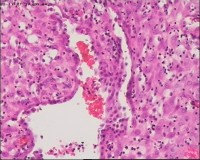

性别

女

年龄

20岁

停经3月,阴道不规则流血7天。

宫刮物

灰白灰红碎组织一堆,大小为7*6*1cm,部分组织呈水泡状

水肿的绒毛和蜕膜,没看到增生的滋养细胞。必要时可做IHC除外部分葡萄胎,并结合临床HCG。

考虑葡萄胎